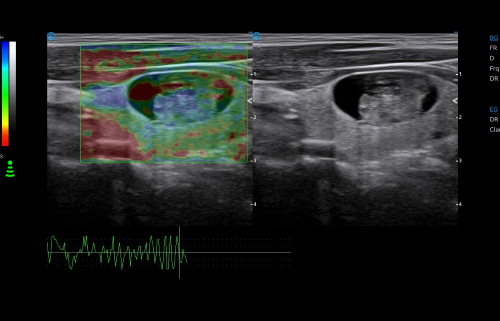

Click on images to enlarge

VS Flow is highly sensitive to low velocity blood flow signal and especially suitable for superficial blood flow examination